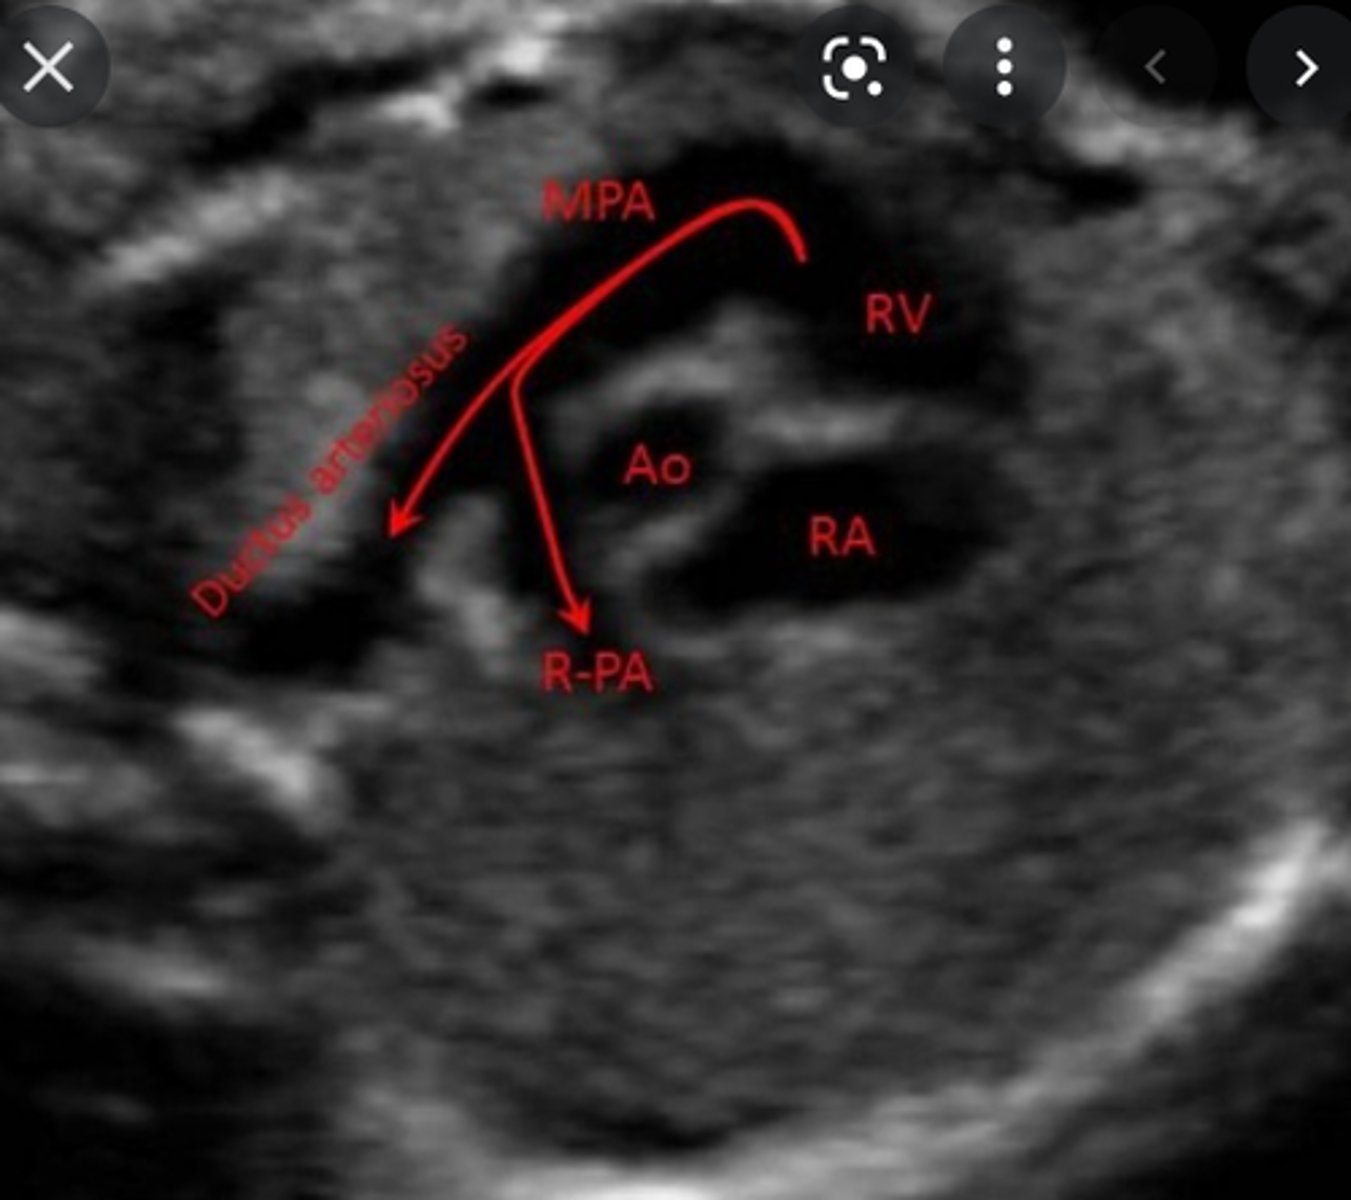

Communication is also open between the aorta and the ___ via the ___

pulmonary artery; ductus arteriosus

tricuspid; right ventricle; main pulmonary artery (MPA)

MPA bifurcates into right and left pulmonary artery branches that lead to their respective ___

Most of this blood passes through the connection of the ___ into the ___; only a very small amount goes to the lungs

ductus arteriosus; descending aorta

If ductus arteriosus communication persists, it is called a ___

patent ductus arteriosus